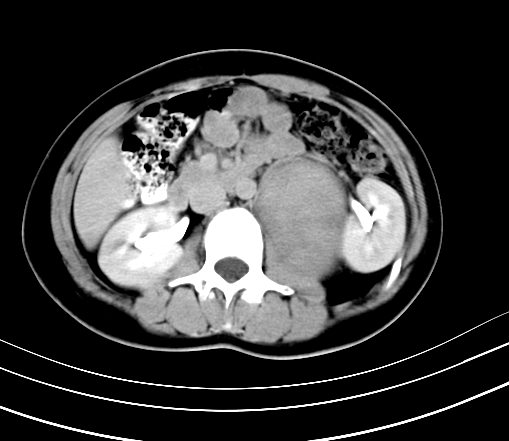

腹部平扫